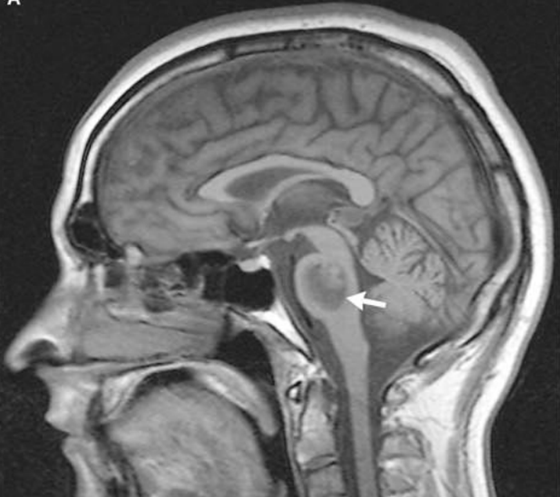

19 y/o man collapsed playing basketball. He was noted to have a seizure consisting of right arm shaking and then fell to the ground without protecting himself.

On arrival noted to have weakness on his right side, reactive pupils, positive corneals and cough. Not following commands or moving spontaneously.

Vitals: 220/120, HR 45, RR 12 (intubated)

AVM rupture presenting with seizure

(most present with seizure. if you have young pt that has seizures and looks like large stroke in brain; think AVM)